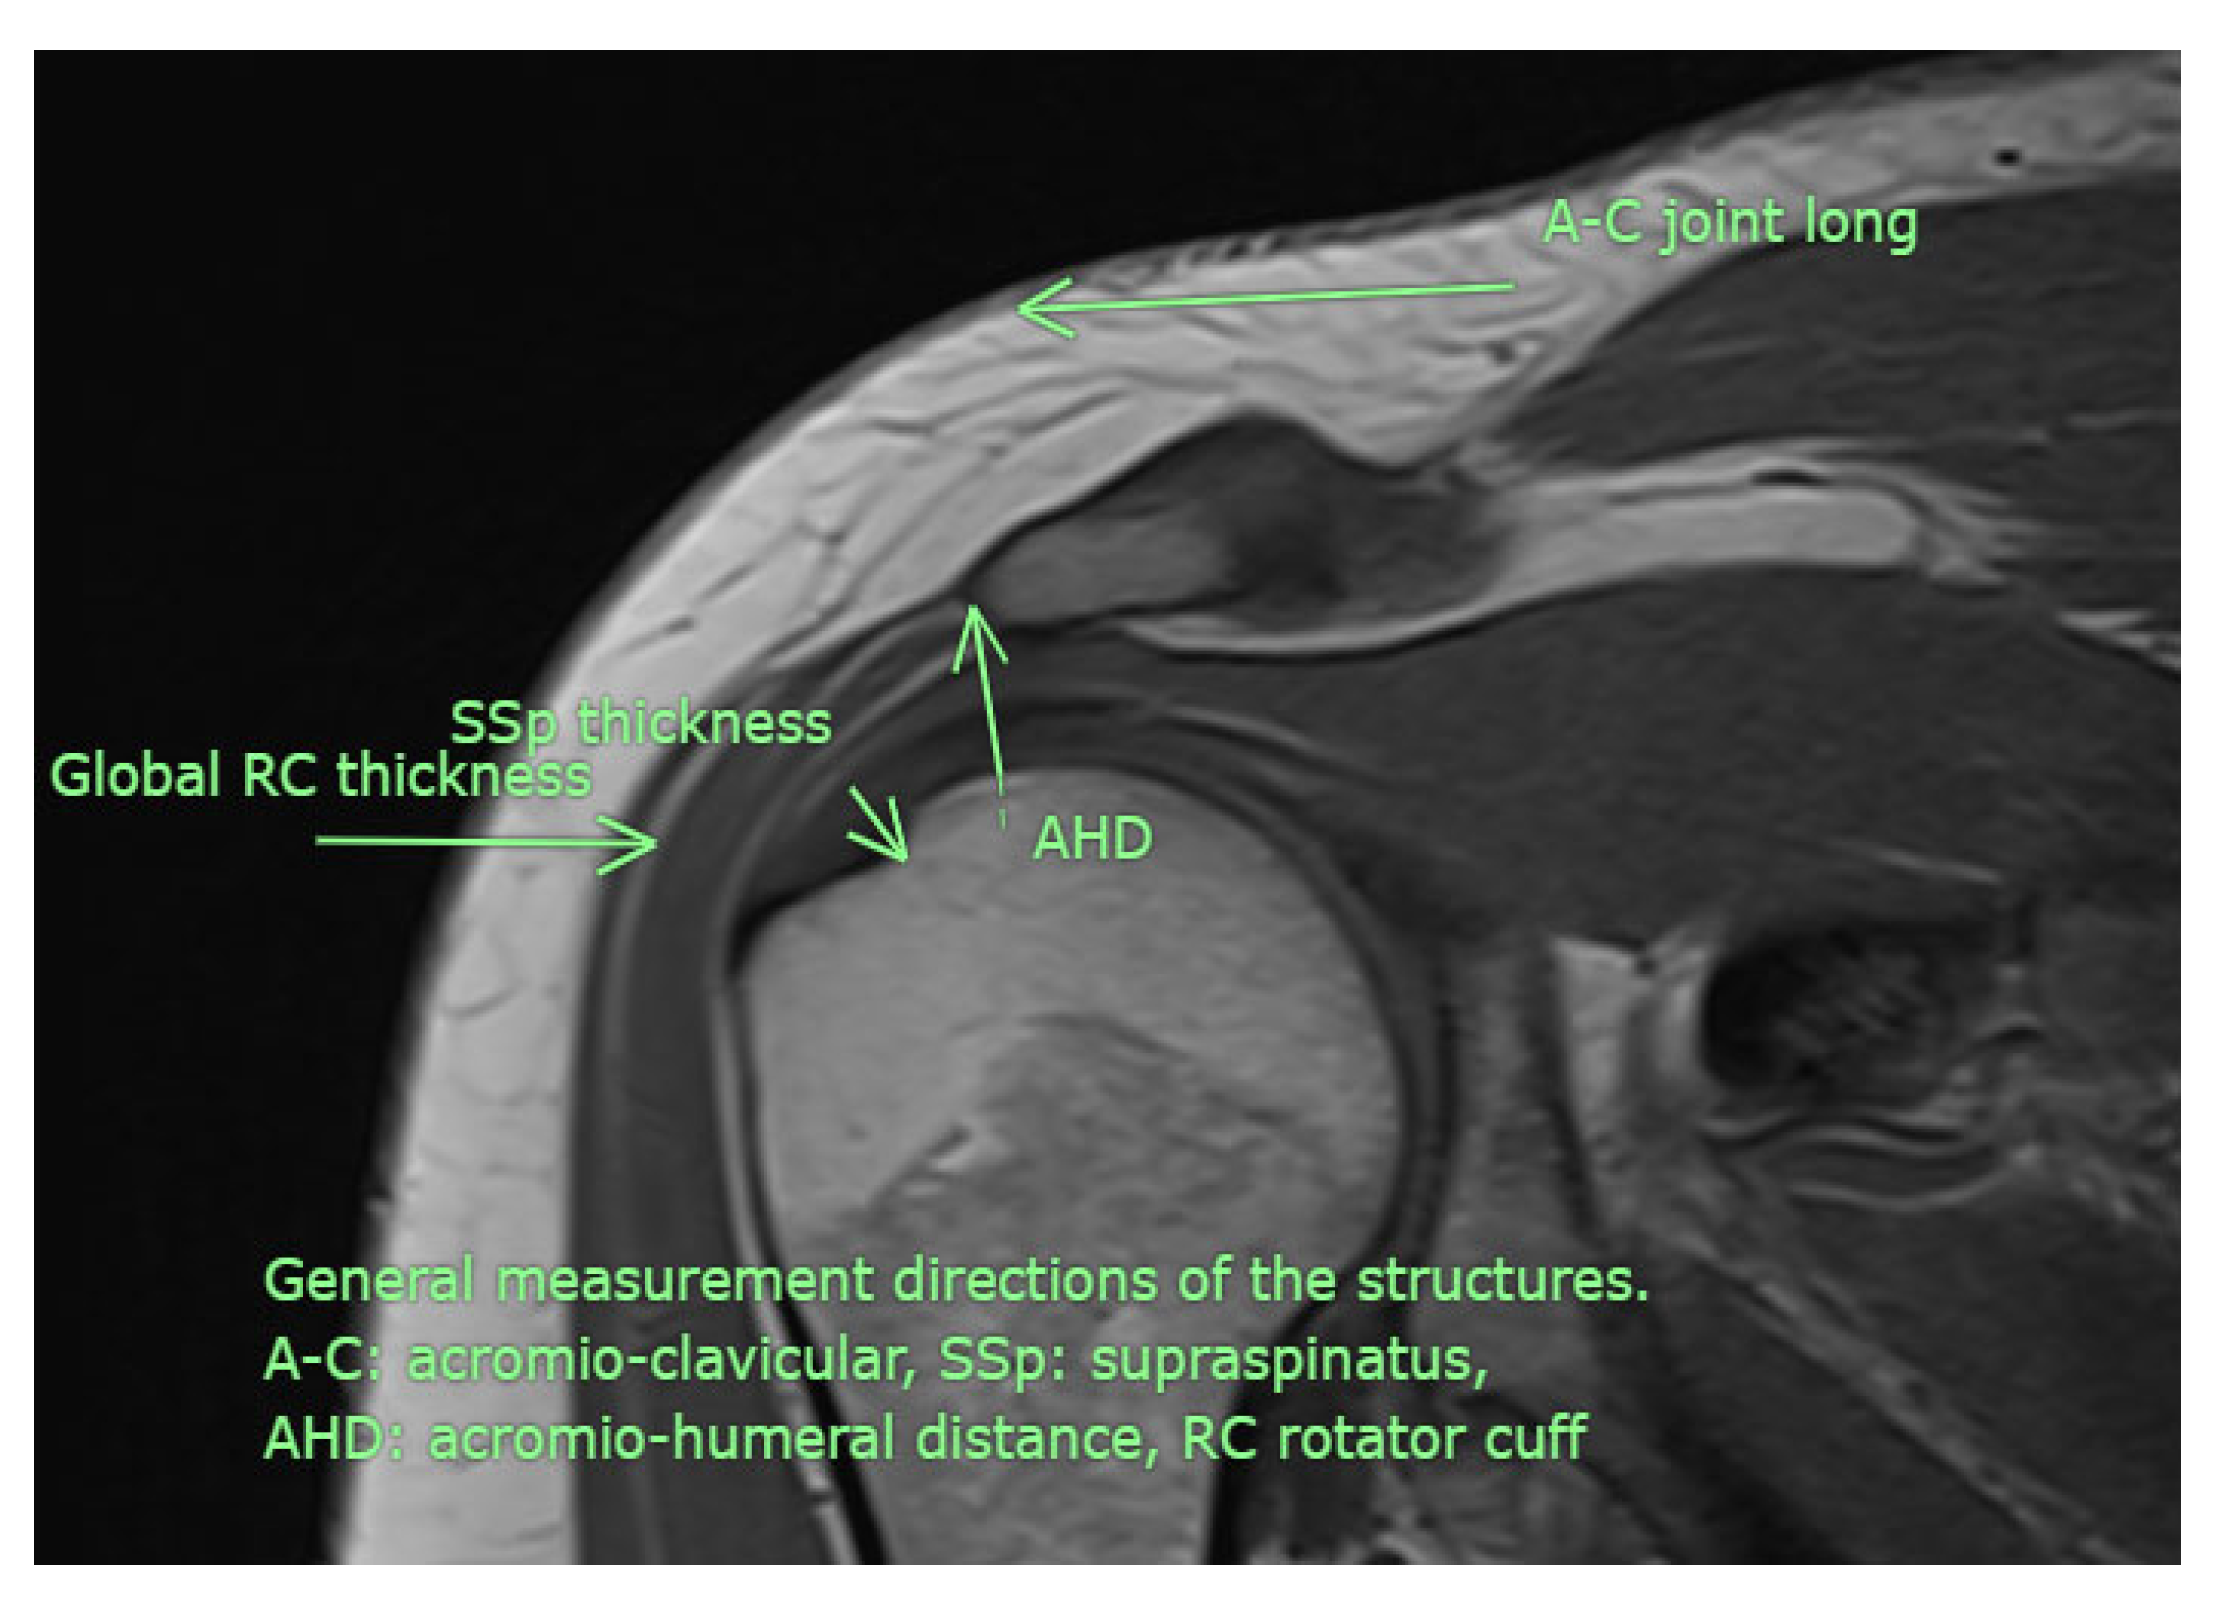

Figure 3. Although examined in all available directions, this MRI image illustrates the measurement sites used in the study (personal archive).

All USG evaluations were performed by a physical medicine and rehabilitation specialist with +30 years of experience in musculoskeletal USG using a GE LogiqP6 Pro device GE Ultrasound Korea, Gyeonggi, Republic of Korea and a linear transducer. Imaging was performed using standard shoulder sections while the patients were in a sitting position with an elbow flexed and an arm internally rotated and laid on the anterior thigh. We laid the probe on the coronal plane on the acromio-clavicular joint. We then moved it laterally to detect acromial-end and subacromial structures, including the subacromial bursa (SB), rotator cuff, and humeral head. Beneath the SB is the supraspinatus tendon (SSp), which attaches to the tuberculum majus of the humerus. The arm was rotated and abducted to examine the tendinous integrity and motion of the SSp. To measure the AHD and ensure standardization, a perpendicular line was drawn from the most lateral tip of the acromion to the head of the humerus, yielding an automatic value via USG-software vR2.0.5 (Figure 2 and Figure 3). In this position, we evaluated the supraspinatus and RC and measured their thicknesses on the short axis. The thickness of the SB was noted. Then, the probe was retracted, and the internal structure of the infraspinatus (Isp) and its thickness were measured. Notably, the teres minor, though difficult to discriminate, is at the posterior end of the ISp. Then, the probe was moved to the short axis to examine the biceps tendon. Here, the probe was turned to the longitudinal axis to evaluate the long biceps tendon and determine its thickness. The probe was then moved to the back side on the short axis to examine the labrum, glenoid bone, humeral head, and joint capsule. If the probe is turned longitudinally, the muscle bellies and myo-tendinous junctions of the RC muscles can be seen. Subsequently, the arm was externally rotated, and the probe was again placed medial to the biceps tendon to expose the tuberculum minus, subscapularis tendon, and anterior acromion, along with the coracoacromial ligament. Then, we positioned the arm posteriorly on the back pocket. The measurements regarding the SSp, Isp, and RC were repeated and recorded. During the examination, the acromioclavicular joint, RC tendons (supraspinatus, infraspinatus, subscapularis, and teres minor), long-head biceps tendon, SB, and related structures were evaluated in all planes. Tendon thickness, the presence of subacromial effusion, ruptures, tendinous degeneration, contour irregularities, RC integrity, and homogeneity were examined. Measurements were performed before (baseline) and after the treatment (post-tr).